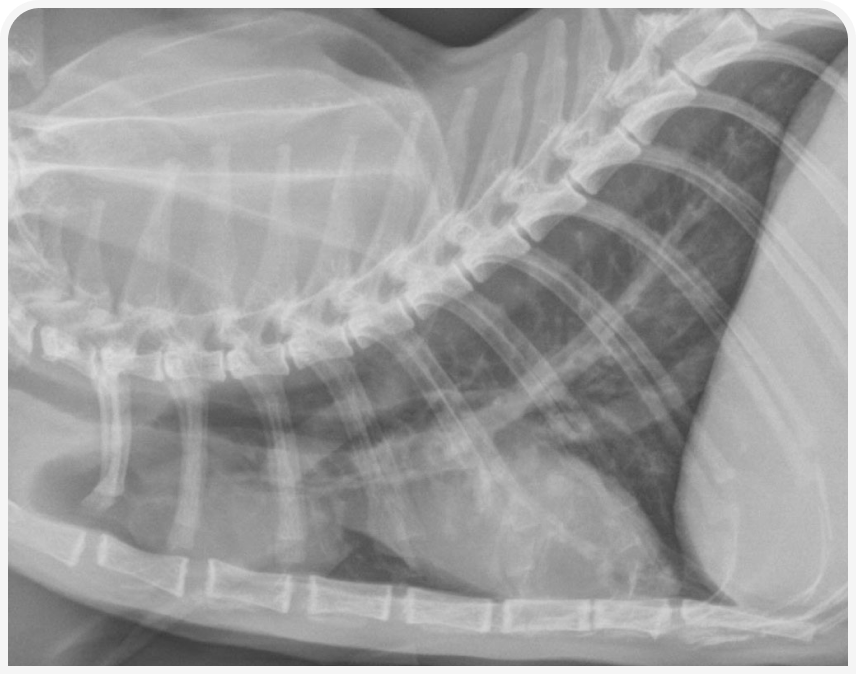

При рентгенографии органов грудной клетки можно выявить четко визуализируемое объемное образование в средостении (Рисунок 1), хотя иногда значительный плевральный выпот может затруднить визуализацию или сделать ее невозможной до тех пор, пока его не дренируют (Рисунок 2), поэтому могут потребоваться повторная рентгенография или УЗИ (Рисунок 3).